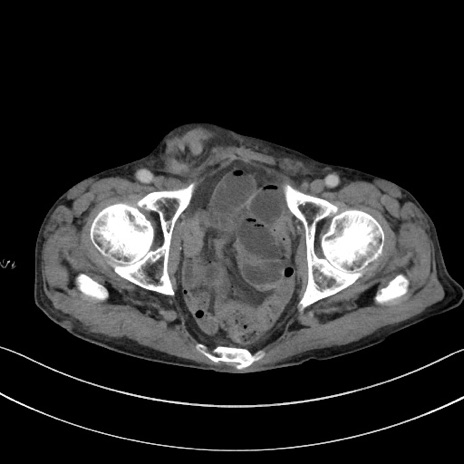

症例3(横断像)

【症例】 70歳代男性

【主訴】右鼠径部腫瘤、疼痛

【現病歴】本日朝より上記主訴あり、受診。

【既往歴】膀胱癌にて膀胱全摘、両側尿管皮膚瘻

【データ】WBC 5600、CRP 0.56